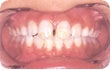

Alteração que ocorre devido ao excesso de ingestão de flúor, durante a formação dos dentes.

Ela se manifesta principalmente pela alteração de cor do esmalte, que pode assumir uma tonalidade esbranquiçada ou exibir pequenas manchas ou linhas brancas. Nos casos mais graves, adquire uma coloração acastanhada ou marrom, podendo haver perda de estrutura dental; nesses casos, torna-se mais friável, mais fácil de desgastar fisiologicamente. Muitos trabalhos apontam como causa da fluorose a utilização de gotas e comprimidos contendo flúor, inclusive muitos complexos vitamínicos recomendados pelos pediatras. Atualmente, a maior causa de fluorose é a ingestão de produtos fluoretados em locais onde já existe água fluoretada, sendo que o mais comum é o dentifrício fluoretado, que muitas crianças engolem durante a escovação. O enxaguatório contendo flúor também poderá contribuir, se for indicado para crianças que ainda não tenham controle adequado da deglutição.